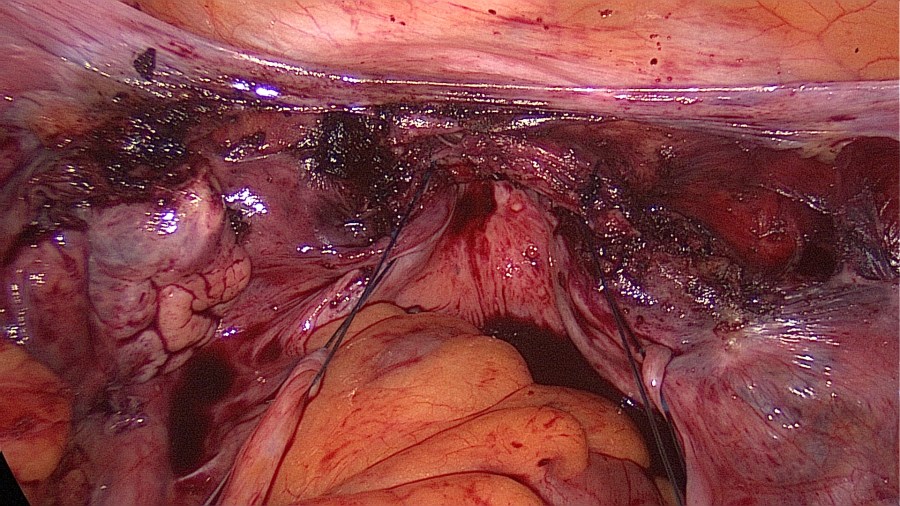

The patient came to us for removal. In our work-up we asked for a preoperative low-dose abdomen CT, which verified intraperitoneal lie of the IUD and excluded bowel involvement.

Interestingly, the patient had experienced the desired amenorrhea for almost 5 years, despite the fact that the IUD was lying inside the greater omentum and not inside the uterus.